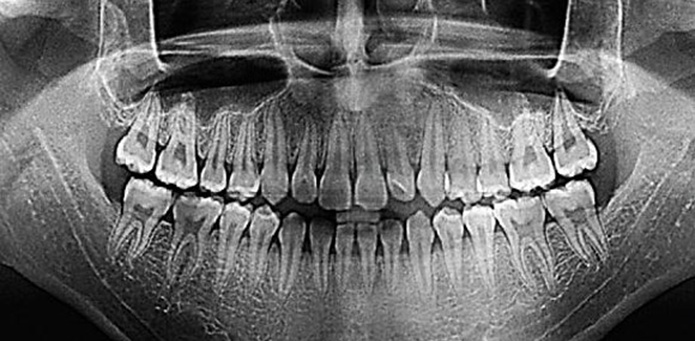

Одно из лучших средств для выявления патологий - это компьютерная томография. Верхняя и нижняя челюсть подвергается исследованиям, если имеются неприятные ощущения и боль в ней во время движения. Технология исследования позволяет более эффективно использовать свойства рентгеновского излучения. В процессе сканируются сотни слоёв тканей, что в итоге создаёт достаточно чёткую картину высокого разрешения.

Если имеются проблемы, то чёткие рентгеновские снимки позволяют врачам точно определить причину недугов. Они в дальнейшем уже назначают эффективное лечение или различные восстановительные процедуры. Цена дентальной компьютерной томографии остаётся достаточно низкой, поэтому популярность подобных исследований становится только выше.

Современное оборудование позволяет получать чёткие снимки, однако для этого нужно следовать определённым инструкциям. Обычно пациента консультируют заранее и объясняют ему все основные особенности. Само по себе подобное исследование не вызывает никаких болезненных ощущений, но у некоторых может проявляться чувство тревоги. Особо впечатлительным людям лучше принять седативные препараты, потому что во время сканирования нужно оставаться неподвижным.

Во время КТ челюсти для стоматолога аппарат фокусируется на данной области. Компьютерный томограф состоит из специальной кушетки, на которую помещается пациент, а также подвижного сканера. После запуска он начинает вращаться и делать серию снимков. В дальнейшем информация обрабатывается на компьютере с помощью специального программного обеспечения. Томографический купол содержит большое количество разнообразных датчиков.

При КТ челюсти, в отличие от других видов исследований, можно пить воду, и нет никаких ограничений по приёму пищи. Ортопантограмма и телерентгенография — это эффективный инструмент диагностики в руках современных врачей.